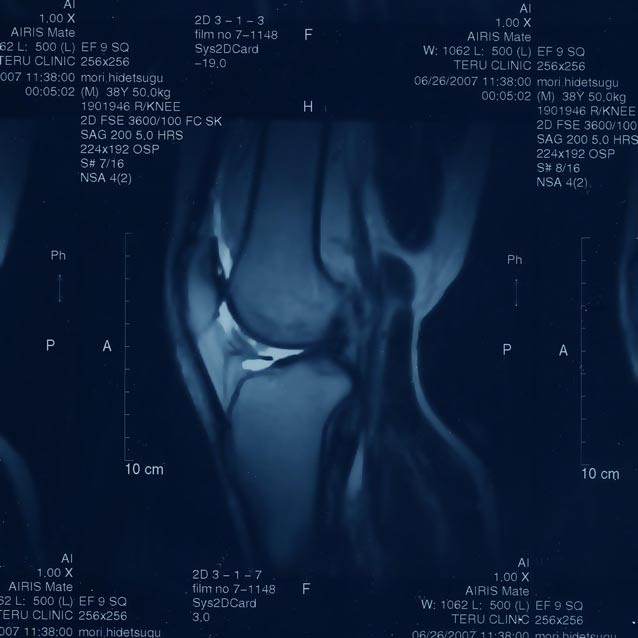

待合室で待つこと、およそ10分。

「ほほ、そんなに早く結果が出るの?」

半信半疑で診察室に入ると、輪切りに展開された自分の右膝が。

コンピュータ処理で自在に右膝の内側に侵入。

出たり入ったりを繰り返しながら、

レントゲンでは見ることのできなかった

軟骨の状態、筋肉の状態、半月板の状態を確認する。

大腿骨がガッチリと脛骨にぶつかり、

その周りを靱帯が支えている。

我ながら、見事な膝の構造体だ。

そこで医者は、半月板の状態を説明しだした。

上からみた断面図と、横からみた断面図を交互させながら、

半月板のカタチを調べてみると…。

どうやら半月板そのものが断絶している…らしい。

このまま放っておいても悪化するばかりで

良くなる保証はないらしい。

核磁気共鳴画像法(Magnetic Resonance Imaging, MRI)

なる生体内撮影を金曜日におこなった。

なんのことはない、2週間前にジョギングで痛めた膝が

なかなか完治しないので、大事をとってスポーツ外科に行ってみたのだ。

レントゲン検査では、膝の複雑な構造をチェックすることが出来なかったので、

日を改めてMRI検査に臨んだわけだ。

高磁場を起こす大きな円盤の下に40分間。

カラダを動かさないように固定しながら、磁力に晒される。

体内のあらゆる細胞が反応しているんじゃないだろうか…

と思わせる強い磁力が、右膝を中心に行ったり来たり。

つま先からアタマの中まで電気風呂に入ったような痺れに襲われる。

意識も朦朧として、指の感覚がなくなり、五指すべてがもぎ取られたような錯覚に。

それでもなんとか高磁場の試練に耐え、痺れたアタマで待合室に。